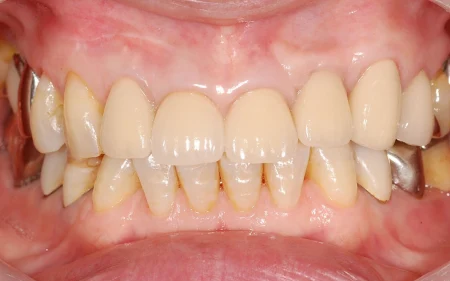

最終的な仕上がりはこのようになりました。